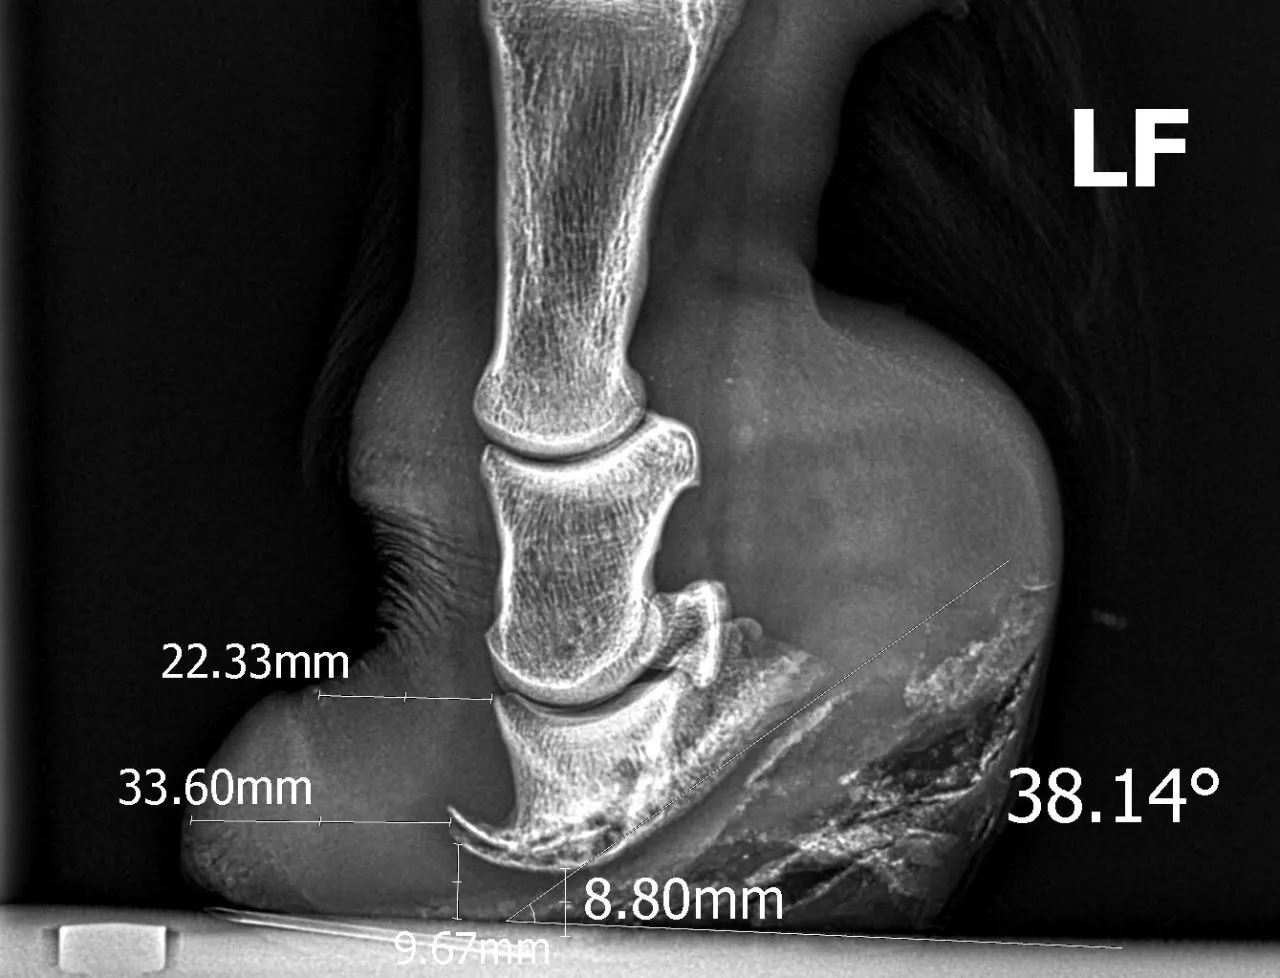

Punkt przełamania, czyli moment, w którym kopyto odrywa się od ziemi, jest niezwykle ważny dla płynnego i zdrowego ruchu konia. Jest to punkt, w którym kopyto „przewraca się” do przodu, zanim cała kończyna zostanie uniesiona. Prawidłowe ustawienie tego punktu, często regulowane przez kowala, jest kluczowe dla minimalizowania obciążeń na stawy i ścięgna. Zbyt długi pazur kopyta (zbyt przesunięty punkt przełamania) zwiększa dźwignię działającą na struktury kończyny, co może prowadzić do przeciążeń i kontuzji. Optymalne ustawienie punktu przełamania pozwala koniowi na efektywny, swobodny i bezbolesny ruch.

Kowal to jeden z najważniejszych specjalistów w życiu konia, a regularne wizyty (co 6-8 tygodni) są absolutnie niezbędne. Moja wiedza o anatomii pozwala mi świadomie rozmawiać z kowalem, rozumieć jego decyzje i aktywnie uczestniczyć w procesie pielęgnacji kopyt. Prawidłowe werkowanie i, jeśli to konieczne, kucie, ma za zadanie wspierać naturalną mechanikę kopyta. Chodzi o utrzymanie jego prawidłowego kształtu, balansu, optymalnego punktu przełamania oraz funkcji amortyzacyjnych. Dobry kowal potrafi skorygować drobne wady postawy, zapobiec przeciążeniom i zapewnić, że kopyto będzie pracować tak, jak natura je zaprojektowała. To inwestycja w zdrowie i komfort konia.